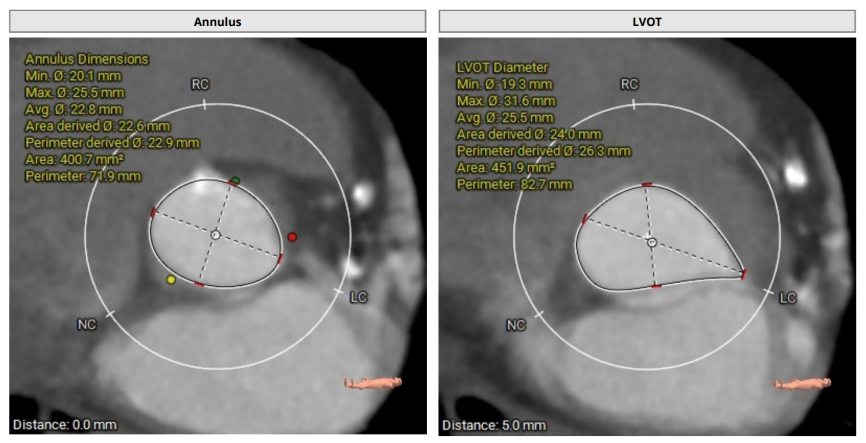

术前CT

术前CT(上下滑动查看更多图片)